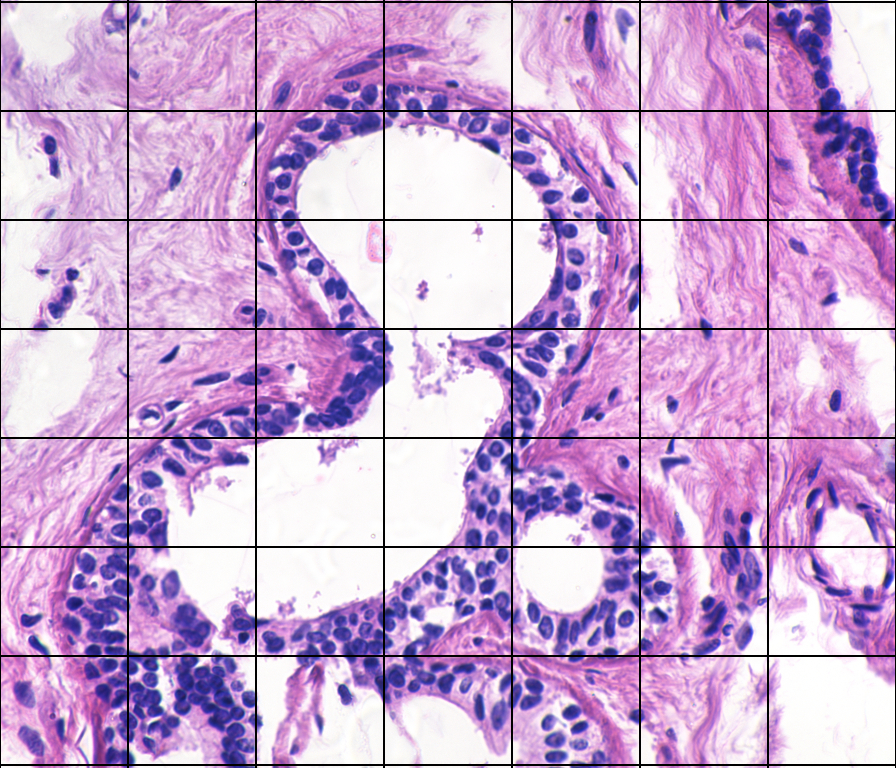

Figure 1a shows an image (bag), k𝑘k, of benign breast tissue [1], divided into nksubscript𝑛𝑘n_{k} segments with corresponding feature vectors (instances) 𝐱k1,,𝐱knksubscript𝐱𝑘1subscript𝐱𝑘subscript𝑛𝑘\mathbf{x}_{k1},\ldots,\mathbf{x}_{kn_{k}} [2]. Correspondingly, figure 1b shows malignant breast tissue.

(a) Benign

(b) Malignant

Figure 1: Breast tissue images. The image segments are not labelled.

Breast tissue images (see Fig. 1) with corresponding feature vectors are used as example. Following the procedure in [2], the principal components are used for dimension reduction, and 444-fold cross-validation is used so that f^neg(x)subscript^𝑓𝑛𝑒𝑔𝑥\hat{f}_{neg}(x) and f^pos(x)subscript^𝑓𝑝𝑜𝑠𝑥\hat{f}_{pos}(x) are fitted only to the instances in the training folds. For pdf estimation, GMMs are fitted to the first principal component, using an EM-algorithm, with number of components chosen by minimum AIC. In addition, KDE as in Section 5.1, and KDE with Gaussian kernel and optimal bandwidth [41] is used.